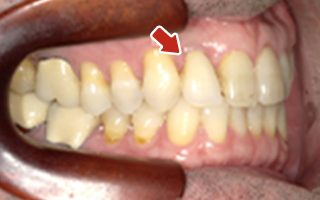

Before

After

| 55歳 男性 | |

|---|---|

| 主訴 | 前歯でしか咬めなく、食事を摂るのに非常に困難で辛い |

| 処置内容 | 上顎6本、下顎3本 |

| 治療費用 | 上顎: 約230万(税込) 下顎: 約120万(税込) |

| 治療期間 | 上顎: 1年(仮歯まで8ヶ月) 下顎: 8ヶ月(仮歯まで5ヶ月) |

| リスク | 上部構造物、仮歯の破折、術後の腫れ(3日)、人工歯根脱落リスクがあります |